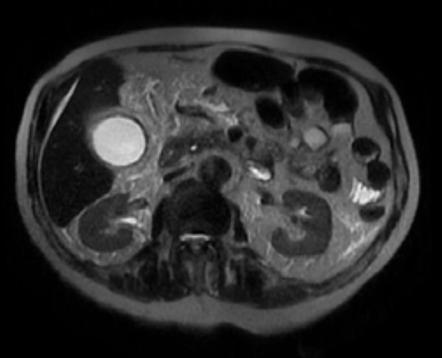

Магнитно-резонансная томография при остром холецистите выявляет следующие анатомические признаки:

На Т2-взвешенных изображениях визуализируются гиперинтенсивные участки отёка стенки желчного пузыря и перихолецистической клетчатки с расширением просвета пузыря.

В режиме динамического контрастного усиления определяется усиление стенки желчного пузыря, свидетельствующее об активном воспалительном процессе и сохранении васкуляризации.

В режиме трёхмерной реконструкции визуализируются размеры желчного пузыря, толщина его стенки и пространственные взаимоотношения с соседними структурами.